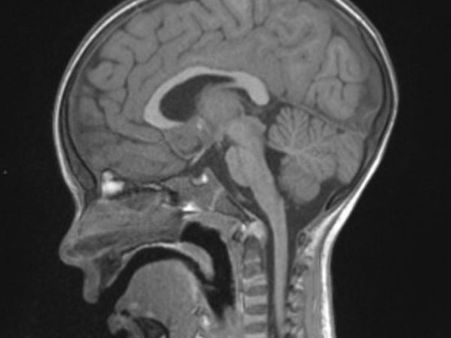

Diagnosis Of Cerebral Palsy

A

MRI

of

the

brain

is

usually

undertaken.